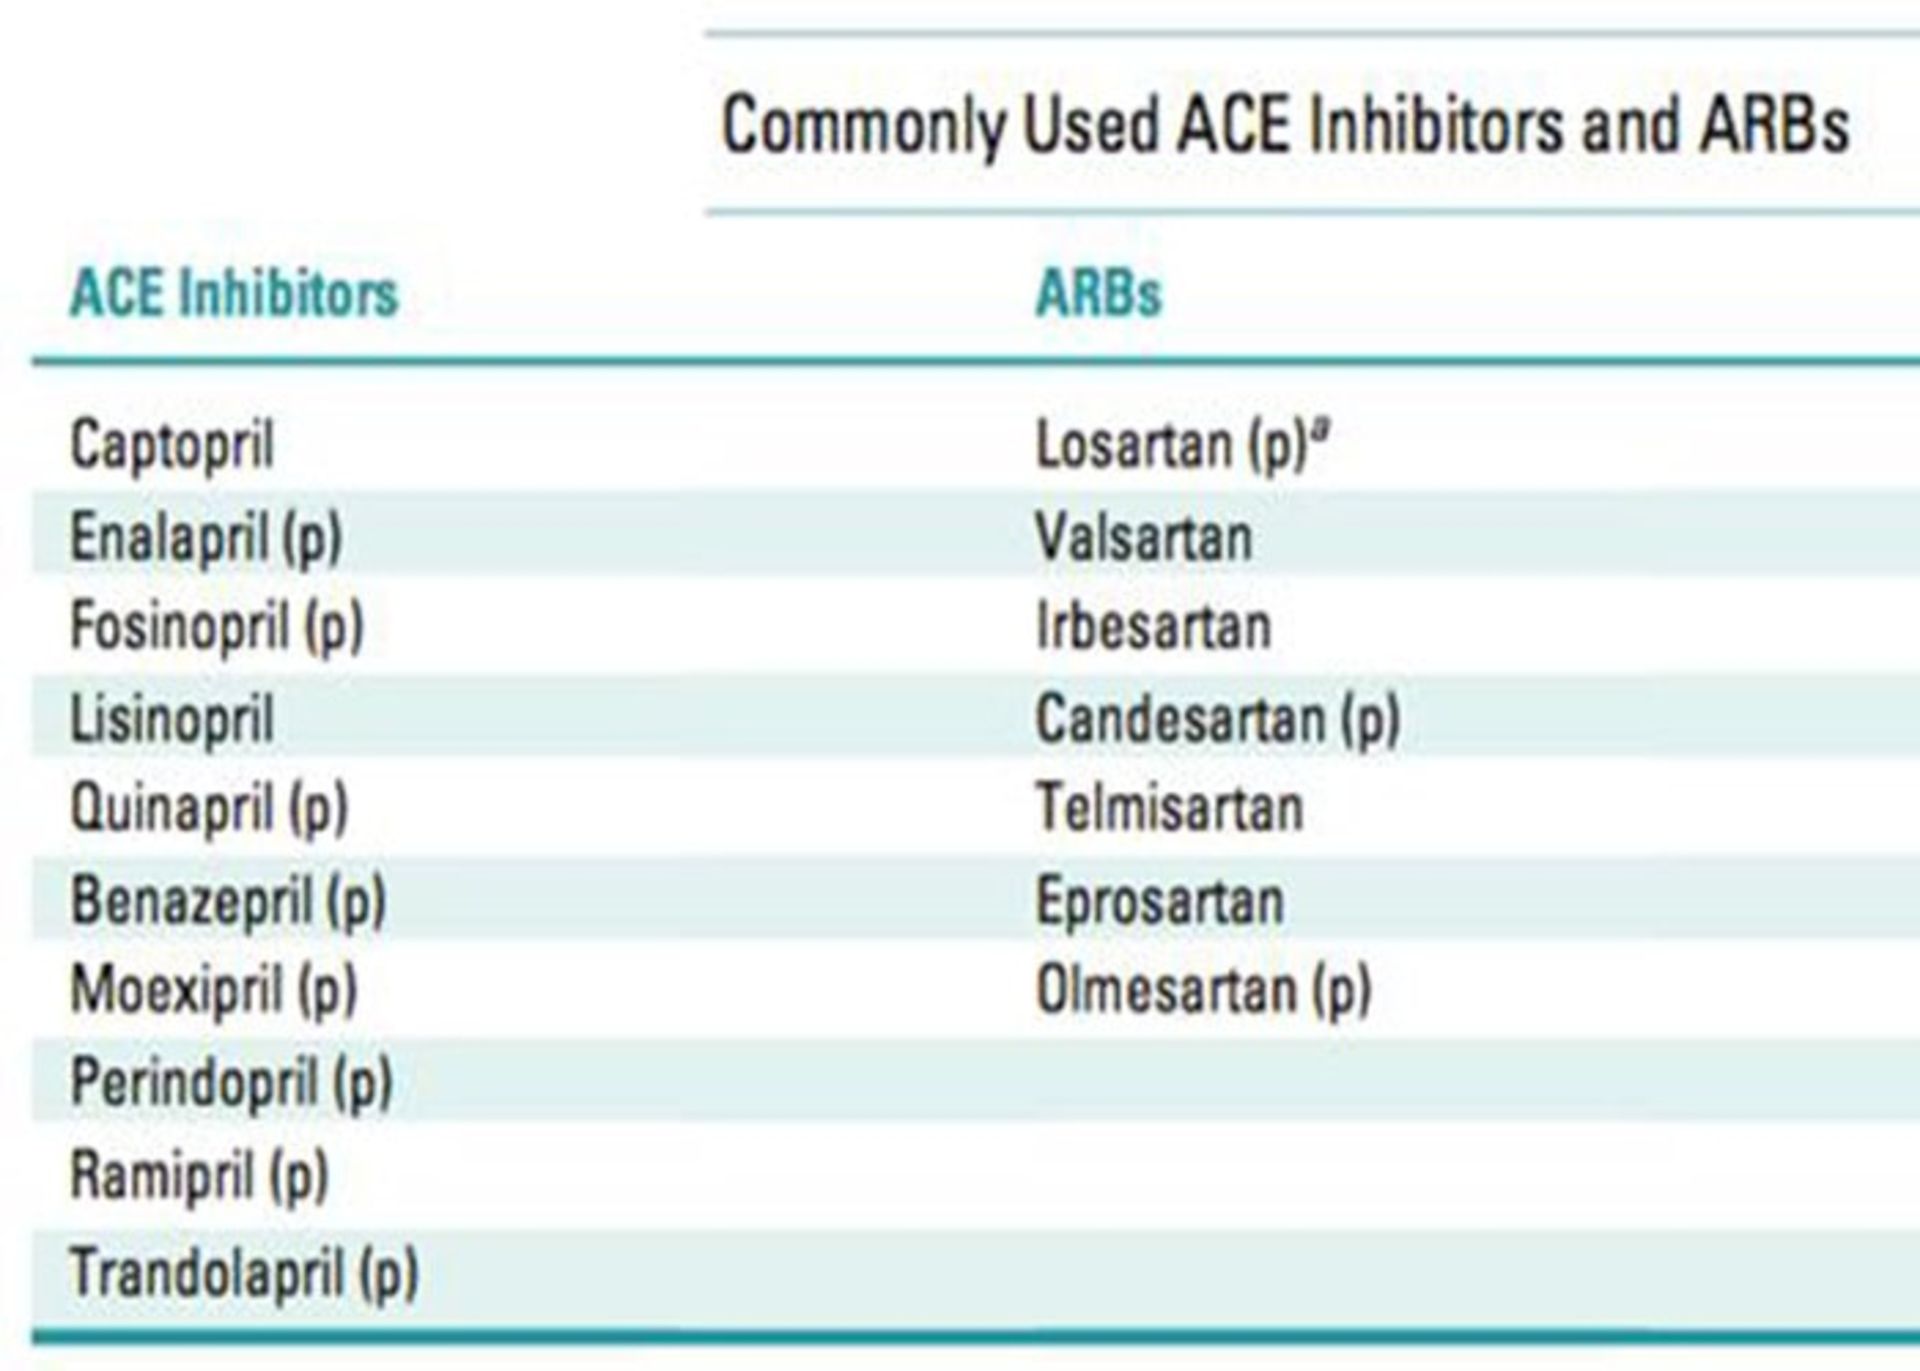

بر اساس نتایج یک مطالعهی مشاهدهای که در ژورنال The BMJ منتشر شده است، داروهای مهارکننده آنزیم تبدیلکنندهی آنژیوتانسین (ACE- inhibitors) در مقایسه با داروهای فشار خون دیگری که داروهای مسدودکنندهی گیرندهی آنژیوتانسین (ARBs) نامیده میشوند، با افزایش خطر ابتلا به سرطان ریه همراه هستند.

پژوهشگران با استفاده از اطلاعات موجود در پایگاه دادهی مراقبتهای اولیه بریتانیا بیش از ۹۰۰ هزار فرد بالغ را شناسایی کردند که از سال ۱۹۹۵ برای فشار خون بالا تحت درمان با یکی از انواع داروهای کنترل فشار خون قرار گرفته بودند. از این میان، بیش از ۳۳۵ هزار بیمار با استفاده از داروهای گروه مهارکنندههای ACE تحت درمان قرار گرفته بودند، ۲۹ هزار بیمار از داروهای گروه ARB استفاده کرده بودند و ۱۰۱ هزار بیمار هم از هر دو گروه دارو استفاده کرده بودند. داروی رامیپریل (۲۶ درصد) رایجترین داروی گروه مهارکنندههای ACE بود و پس از آن لیزینوپریل (۱۲ درصد) و پریندوپریل (۷ درصد) قرار داشتند.

طی پیگیری یک دورهی ۶ ساله، سرطان ریه در ۰/۸ درصد (۷۹۵۲ مورد) از این ۹۰۰ هزار فرد تشخیص داده شده بود. پس از در نظر گرفتن اثر عواملی نظیر مصرف سیگار و دیگر عوامل تاثیرگذار ممکن، شانس ابتلا به سرطان ریه در نتیجهی مصرف داروهای مهارکنندهی ACE در مقایسه با داروهای گروه ARB، در حدود ۱۴ درصد بیشتر بود. البته تجزیهوتحلیل دیگری نشان داد که استفاده از مهارکنندههای ACE برای کمتر از ۵ سال با افزایش خطر ابتلا به سرطان همراه نیست. اگرچه این مطالعه نشان میدهد که افزایش خطر ابتلا به سرطان ریه تا زمانی که بیمار برای مدت ۵ سال تحت درمان داروهای مهارکنندهی ACE قرار نگیرد، آشکار نمیشود ولی این احتمال در نتیجهی مصرف این دارو برای مدت ۱۰ سال، بیشتر میشود (۳۱ درصد افزایش خطر). پژوهشگران در مطالعهی خود توضیح دادهاند که استفاده از مهارکنندههای ACE موجب تجمع برادیکینین در ریهها میشود؛ مادهای که بهنظر میرسد موجب تحریک رشد سرطان ریه میشود. علاوهبر این، مصرف مهارکنندههای ACE احتمالا منجر به افزایش سطوح ترکبیبی به نام مادهی P میشود؛ مادهای که در سلولهای سرطانی ریه تولید شده و با رشد تومور ارتباط دارد.

از آنجایی که مهارکنندههای ACE بخش زیادی از داروهای تجویزی کنترل فشار خون را تشکیل میدهند، این نتایج میتواند موجب نگرانی تعداد کثیری از بیماران شود و باید به این نکته توجه کرد که این نتایج حاصل یک مطالعهی کنترلشده نبوده و نتایج یک مطالعهی مشاهدهای هستند. محدودیتهای مهم این مطالعه که باید به آنها اشاره شود؛ عبارتند از فقدان اطلاعات مربوط به وضعیت اجتماعیاقتصادی، رژیم غذایی، میزان قرارگیری در معرض موارد سرطانزای ریه مثل آزبست و رادون و همچنین نبود اطلاعات مرتبط با سابقهی خانوادگی ابتلا سرطان ریه در بیماران. نویسندگان همچنین دارای اطلاعات دقیقی در مورد تعداد سالهای مصرف سیگار که عامل مهمی برای بروز سرطان ریه است، نبودند.

با این حال اگرچه مهارکنندههای ACE داروهای بسیار موثری برای درمان فشار خون بالا در کوتاهمدت هستند، نگرانیهایی در مورد استفادهی طولانیمدت از آنها بهویژه در ارتباط با بیماری سرطان ریه بهوجود آمده است. شواهد بیوشیمایی، نشاندهندهی ارتباط بالقوه بین استفاده از مهارکنندههای ACE و افزایش خطر ابتلا به سرطان ریه است. قطعا در مورد هر بیمار تحت خطر سرطان ریه، مزایای مرتبط با مصرف داروهای مهارکنندهی ACE برای کاهش فشار خون و خطر مشکلات قلبی باید در برابر خطر ابتلا به سرطان ریه سنجیده شود و مورد ارزیابی قرار گیرد. کلائوس لسنو، متخصص ریه از بیمارستان لنوکس هیل میگوید:

بیماران باید در مورد مزایا و معایب مصرف داروهای مهارکنندهی ACE با پزشک معالج خود مشورت کنند. یکی از گزینههای درمانی ممکن، تغییر دارو به سمت استفاده از داروهای گروه ARB است. تاکنون ارتباطی بین بروز سرطان ریه و مصرف این دارو گزارش نشده است. دکتر کرونین فنتون با اشاره به اهمیت این یافتهها لزوم انجام مطالعات بیشتری را برای آزمایش این نتایج خاطرنشان کرد. اگرچه افزایش نسبی ۱۴ درصدی در شیوع سرطان ریه ممکن است به مفهوم وجود یک خطر مطلق بزرگ نباشد ولی این یافتهها با توجه به حجم وسیع مصرف این داروها در کل جهان از اهمیت زیادی برخوردارند. کرونین ادامه میدهد :